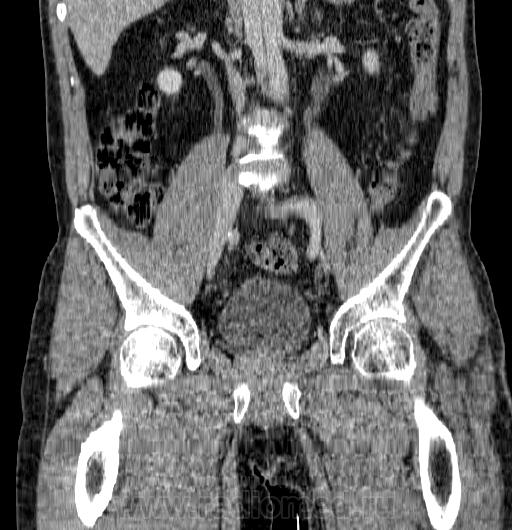

Подскажите коллеги! Больной находится на лечении в х/отд , оперирован в 10 году АБШ справа, н/к 2Б, паравазальный инфильтрат правой паховой области, неспецифический аортоартериит. Окклюзия п/вздошных артерий с обеих сторон, ампутационная культя левой конечности. Что Вы сможете сказать по проведенному исследованию- проводили по протоколу бр полости с захватом паховой области. На Протоколе сосудов таза исследование не получилось. Хирург запросил уточнить характер инфильтрата и состояние п/вздошн и бедренных артерий.

Сосуды смотрю не часто, поэтому, чем смогу... Поздние нагноения являются третьей причиной поздних осложнений после операций на аорте и сосудах нижних конечностей, так что, на мой взгляд, можно писать абсцесс в правой паховой области и расценить как нагноение протяженный инфильтрат и  скопление жидкости  вокруг шунта справа. Слева - окклюзия от уровня наружной подвздошной артерии. Интрамуральные гематомы/тромбы в области бифуркации аорты, расслоение брюшной аорты (может и выше, но область исследования ограничена).

Кроме того - крупный конкремент в лоханке левой почки, каликулопиелоэктазия слева. Вот как-то так.

На мой взгляд, против абсцесса отсутствие накопления контраста. Жидкостная плотность видна только в паховой области, там тоже накопления контраста нет. Вероятно была гематома, теперь ее остатки. Ну и на клинику надо ориентироваться, конечно.

Протокол не на сосуды. Надо было взять на аорту и подвздошные артерии.

Расслаивающая аневризма аорты. Окклюзия наружной подвздошной артерии. Коллатеральный кровоток в левую нижнюю конечность через систему внутренней подвздошной артерии.

Только по дайкомам разобралась, где шунт). Даже с учетом погрешности замера плотности, стенка того, на что я думаю как на хронический абсцесс, копит, хоть и очень слабо. Думаю, что в "выше расположенном" сосудистом центре, куда пациента наверняка отправят консультироваться, должны быть архивные данные для сравнения: что раньше было, была ли аневризма, уровень окклюзии и прочее.